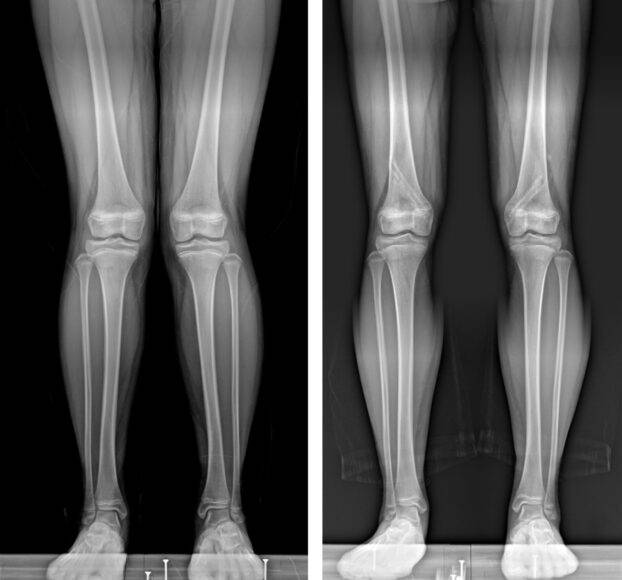

![엑스(X)다리, 오(O)다리. [사진=해운대백병원]](https://img3.daumcdn.net/thumb/R658x0.q70/?fname=https://t1.daumcdn.net/news/202303/07/KorMedi/20230307074026154luhu.jpg)

길고 늘씬한 다리는 여자들만의 바람이 아니다. 요즘엔 남자들도 그렇다. 그런데 만일 무릎이 옆으로 벌어진 오(O)자 다리나 안쪽으로 쏠린 엑스(X)자 다리를 가졌다면?

이럴 때 '성장판 부분 유합술'이 등장한다. 무릎 부위 성장판에 나사못을 직접 삽입하거나 성장판 위 아래 부분을 금속판으로 고정하여 성장판 기능을 일시적으로 억제하는 것. 휜 다리 변형을 교정하는 대표적인 수술법의 하나다.

예를 들어 다리가 오(O)자, 즉 내반슬인 경우는 성장판의 바깥쪽에 금속을 심어 바깥쪽 성장을 억제한다. 그러면 바깥쪽보다 안쪽이 더 빨리 자라게 된다. 반대로 엑스(X)자, 즉 외반슬인 경우엔 성장판 안쪽에 나사못이나 금속판을 넣는다.